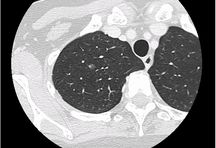

高精度画像診断技術

当院では、各種画像診断装置を導入し、主に各種悪性腫瘍を対象に画像診断、内視鏡的治療、画像介入性低侵襲治療(血管内治療など)、外科的治療に幅広く取り組んでいます。

目的に合った低侵襲な画像診断検査を行い、がんの早期発見および治療に努めています。